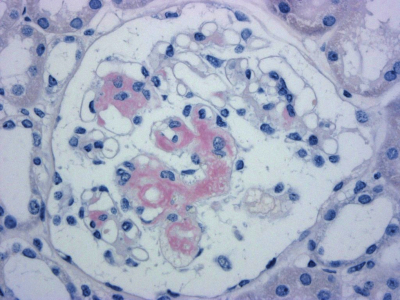

尿所見:蛋白 3+、糖(-)、潜血 2+、沈渣に赤血球 5~10/1視野、尿蛋白 4.5 g/日。血液所見:赤血球 400万、Hb 12.0 g/dL、Ht 36%、白血球5,400、血小板 27万。血液生化学所見:総蛋白 4.7 g/dL、アルブミン 2.0 g/dL、IgG 574 mg/dL(基準 960~1,960)、IgA 269 mg/dL(基準 110~410)、IgM 126 mg/dL(基準 65~350)、総ビリルビン1.0mg/dL、AST 35 U/L、ALT 40 U/L、LD 220 U/L(基準 176~353)、ALP 280 U/L (基準 115~359)、γ-GTP 48 U/L(基準 8~50)、尿素窒素 14 mg/dL、クレアチニン 0.7 mg/dL、尿酸 6.2 mg/dL、HbA1c 5.6 %(基準 4.6~6.2)、総コレステロール 300 mg/dL、トリグリセリド 320 mg/dL。免疫血清学所見:CRP 0.1 mg/dL、抗核抗体陰性。心電図は低電位である。胸部エックス線写真で心胸郭比 54%、肺野に異常を認めない。診断のため腎生検を行った。腎生検のCongo-Red染色標本を別に示す。